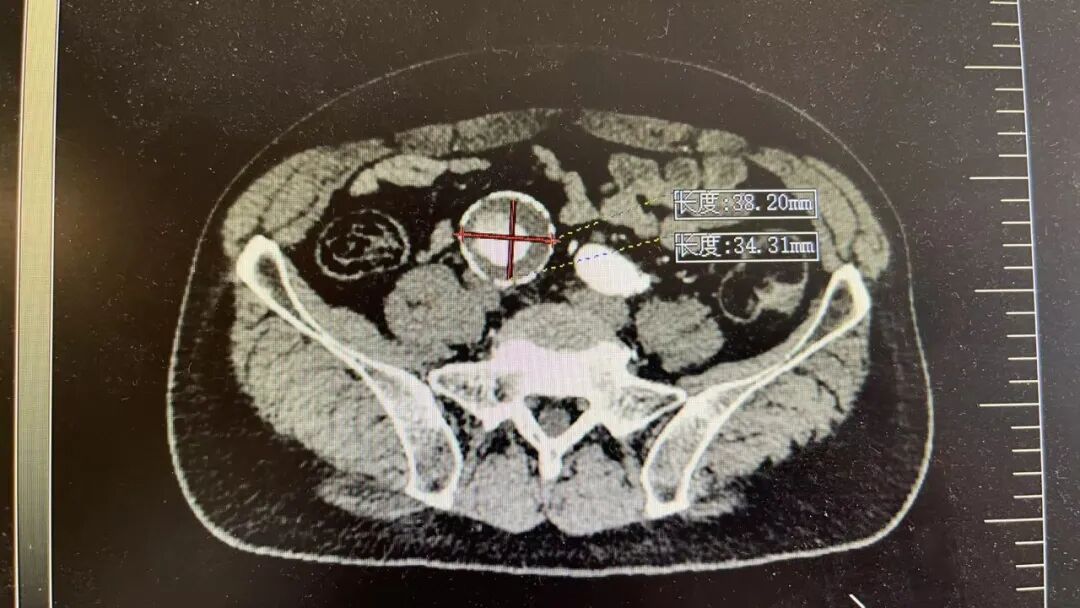

这两位患者情况差不多,他们平日里身体并无明显不适,在一次常规体检中,腹部超声检查结果显示,腹主动脉存在瘤样扩张,进一步检查确诊为腹主动脉瘤,并同时累及双侧髂总动脉,形成髂动脉瘤。

瘤子长在什么位置?腹主动脉是人体腹部最粗大的一根动脉,大致位于肚脐的后面、脊柱的前面,负责将心脏泵出的血液输送到下半身。到了肚脐下方约三四指的位置,它分叉成左右两条髂总动脉,继续向双腿延伸。患者情况比较特殊,动脉瘤不仅累及了腹主动脉主干,还向下延伸到了分叉区域。

北京大学人民医院青岛医院血管外科团队用一个通俗的比喻解释了其中关键:腹主动脉分叉后形成的左右两条髂总动脉,每条又分出一条髂内动脉。这条髂内动脉虽然不算粗,却承担着为臀部肌肉、盆腔器官以及会阴部供血的重任。如果为了拆除动脉瘤,简单地把髂内动脉一起封堵掉,患者术后就可能面临一系列棘手的并发症:臀部肌肉间歇性跛行,走几步路就腿酸乏力;盆腔器官缺血,可能影响肠道和膀胱功能;对于男性患者而言,还会增加性功能障碍的风险。因此,手术的目标很明确,既要拆除动脉瘤,又要保住髂内动脉,最大程度地维护他未来的生活质量。